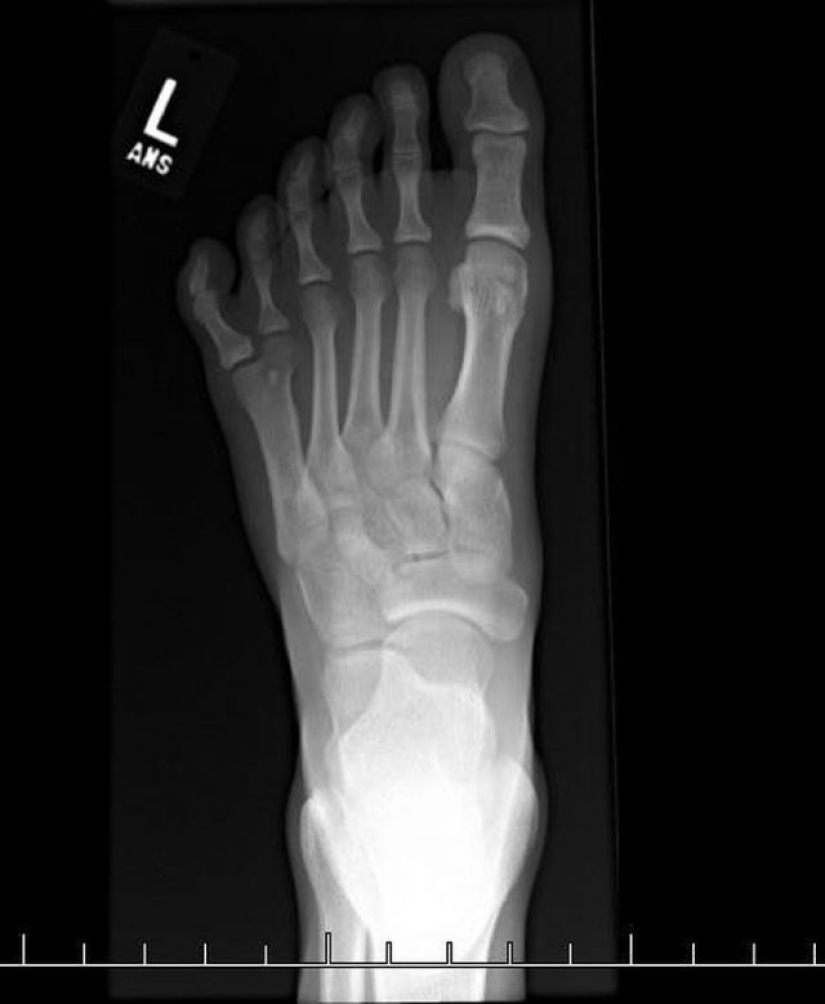

7. Radiografía que muestra 6 dedos.